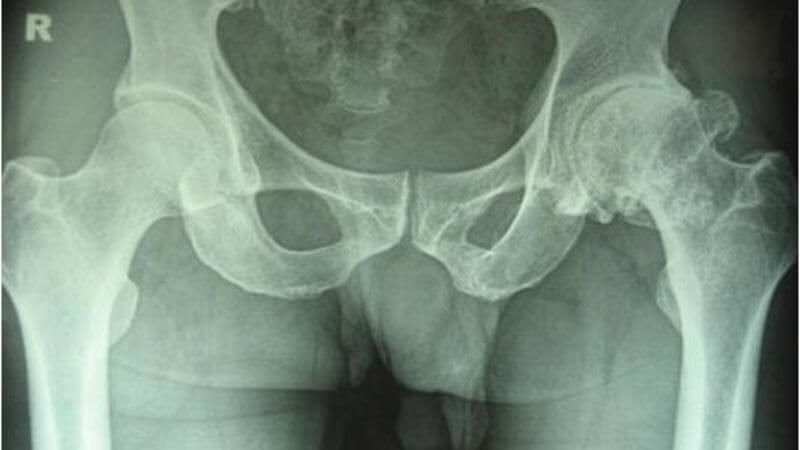

Giai đoạn 3 – Trung bình: Sụn bắt đầu bị xói mòn, hẹp khe khớp rõ rệt, gai nhỏ và xương cứng bên dưới sụn, hình thành nang. Đầu xương đùi và xương hông bắt đầu biến dạng.

xương cùng bên dưới sụn

Hình X-quang cho thấy xương cứng bên dưới sụn, xương chậu biến dạng tại đầu xương đùi bên phải

Biến dạng xương đùi trái

Hình X-quang cho thấy biến dạng xương đùi trái